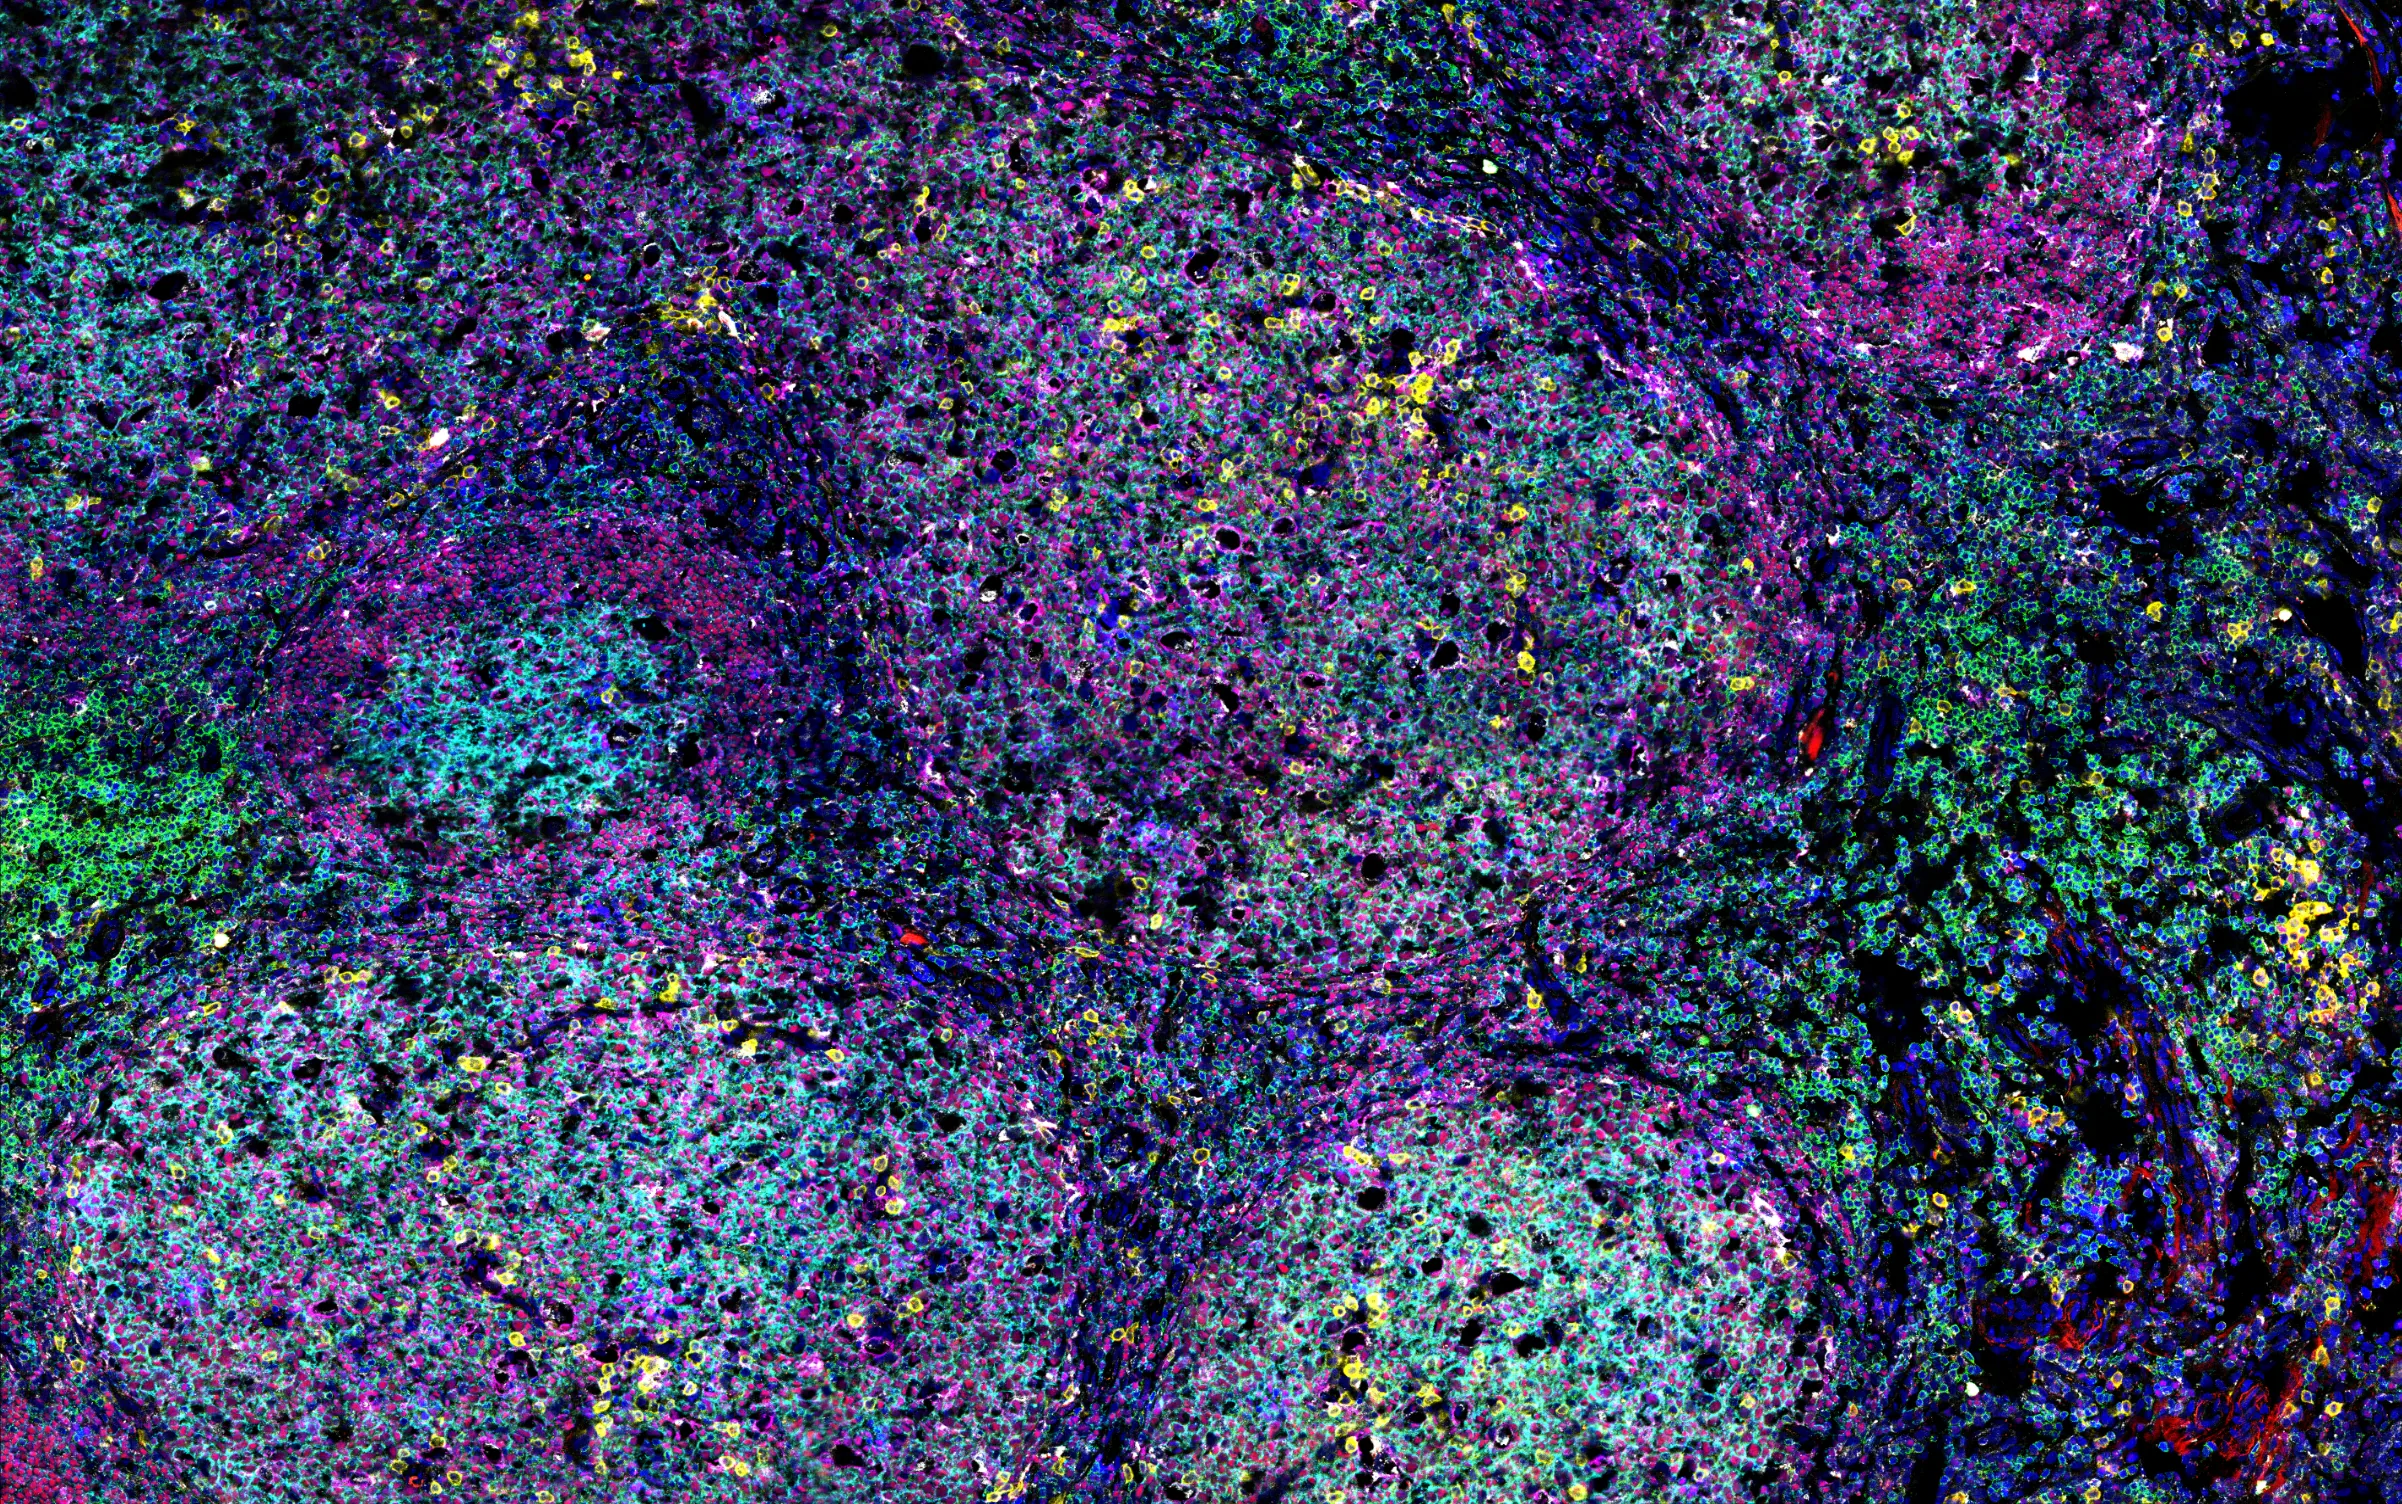

High-dimensional image analysis

To analyze complex tissues such as germinal centers, we use advanced microscopy techniques that generate large, multi-channel datasets. Manual analysis of these datasets is time-consuming and prone to bias. Therefore, we are developing computational pipelines that leverage machine learning and image analysis tools to segment and classify cell types, as well as quantify biologically relevant proteins and glycans within these tissues. This approach enables us to efficiently extract meaningful biological insights from high-dimensional imaging data. Use the slider to compare a raw microscopy image (left) with the corresponding segmented and classified image (right), generated by our analysis pipeline.